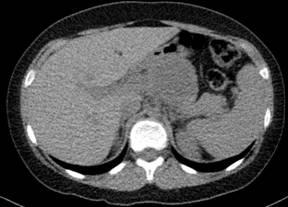

A 13-year-old boy referring postprandial fullness and nausea for the past three months. Weight loss and pain in the upper quadrants of the abdomen recently occurred. Blood workup, including tumor markers, was unremarkable. Abdominal ultrasound (Figure 1) showed a well-circumscribed heterogeneous hypoechoic mass in the region of the pancreatic body/tail. Unenhanced CT (Figure 2) confirmed the pancreatic lesion with a slightly heterogeneous density. No calcifications were identified. T2-weighted MR images (Figure 3ab) showed a 4.8 cm heterogeneously hyperintense lesion in the pancreas, showing a hypointense rim. This rim was also hypointense on T1-weighted images (Figure 3c), consistent with the presence of a tumoral fibrous pseudocapsule. T1-weighted images also showed some internal areas of increased signal intensity compatible with hemorrhage.

Figure 3. Axial fat-supressed (a.) and coronal (b.) T2-weighted MR images show a well-marginated lesion, heterogeneously hyperintense, in the body/tail of the pancreas, with a hypointense fibrous pseudocapsule. c. On an axial unenhanced fat-suppressed T1-weighted MR image the fibrous pseudocapsule is also hypointense (white arrow) and there is an internal peripheral high signal intensity rim (black arrow), a finding consistent with hemorrhage. |

MRI should be considered the best imaging technique for children due to the absence of radiation and its improved capacity for visualizing tumor components [6]. At MR imaging, T1-weighted images show a surrounding hypointense fibrous pseudocapsule and high signal intensity areas corresponding to internal hemorrhage, distinguishing features of solid pseudopapillary tumor [4, 6, 7]. Similar dark rim is also seen on T2-weighted images corresponding to the pseudocapsule [4]. The solid portions of the tumor are usually iso- to hypo-intense to pancreas on T1-weighted images and slightly heterogeneously hyperintense on T2-weighted images [4, 7].